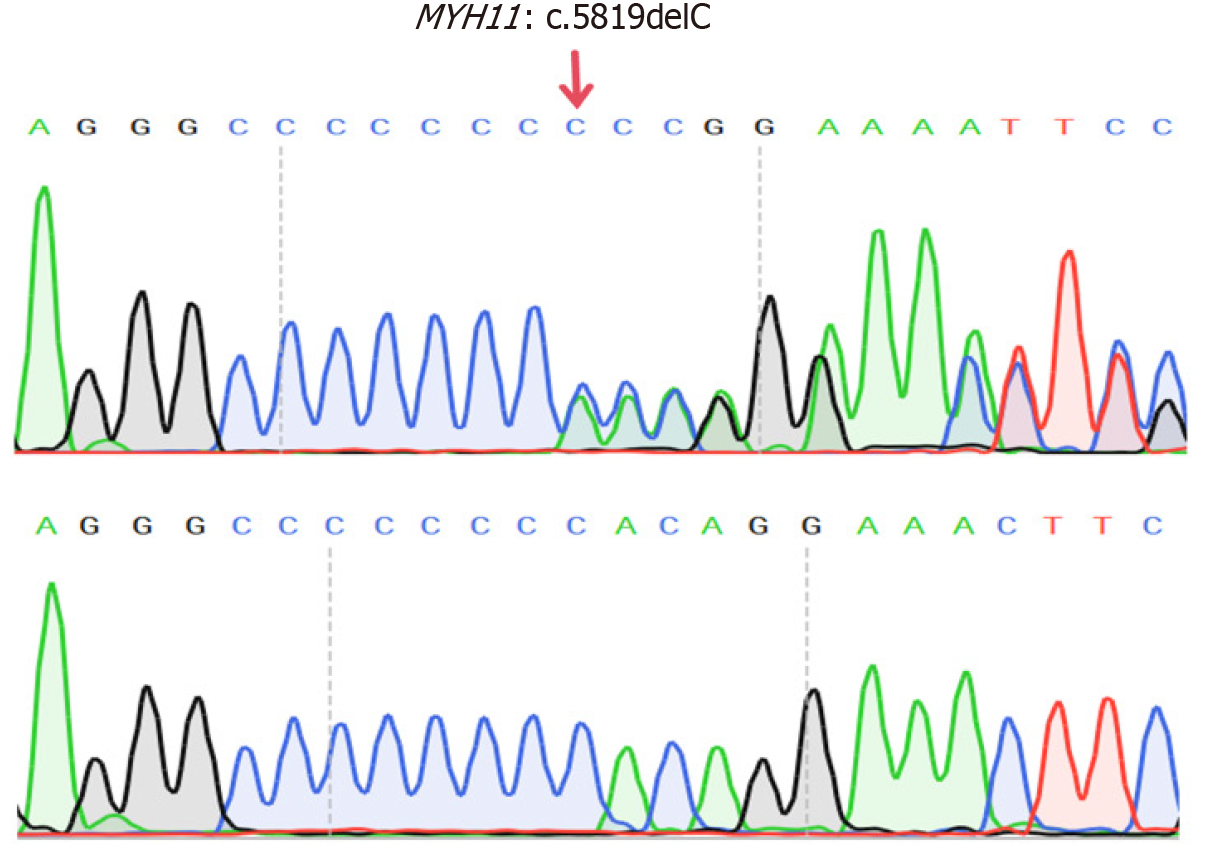

CIPO was diagnosed based on gastrointestinal dysmotility and histopathological findings. Further screening for secondary causes revealed normal glycated HGB levels, thyroid function, and blood cortisol levels. The findings of serum protein and immunofixation electrophoresis, as well as tumor marker levels, were also normal. Antinuclear and anti-double-stranded DNA antibody levels were normal. The celiac disease-related autoantibody panel findings and testing for anti-neuronal antigen antibodies (Ri, Hu, Yo) were negative. Blood tests for tuberculosis infection T-cells, cytomegalovirus, and Epstein–Barr virus were also negative. The hydrogen-methane-carbon dioxide breath test revealed no evidence of bacterial overgrowth in the small intestine. WES identified a heterozygous MYH11 mutation [NM_0010

In the present case, a heterozygous frameshift mutation, MYH11: c.5819del (p.Pro1940HisfsTer91), was identified. This mutation resulted from the deletion of a nucleotide at position 5819 within the gene’s coding sequence, resulting in a frameshift mutation. Consequently, the original stop codon was lost, and a new stop codon was generated at the 91st downstream codon. This led to the addition of 90 extra amino acids at the C-terminus of the MYH11 protein, altering its local three-dimensional structure and contributing to disease pathogenesis[16]. To date, five case reports have identified heterozygous MYH11 mutations in patients with CIPO. In 2019, Dong et al[17] reported on a large 13-member family diagnosed with the CIPO phenotype. Most of the family members presented with megacystis and required long-term self-catheterization. WES analysis of the seven affected individuals revealed a shared MYH11 c.5819del (p.Pro1940